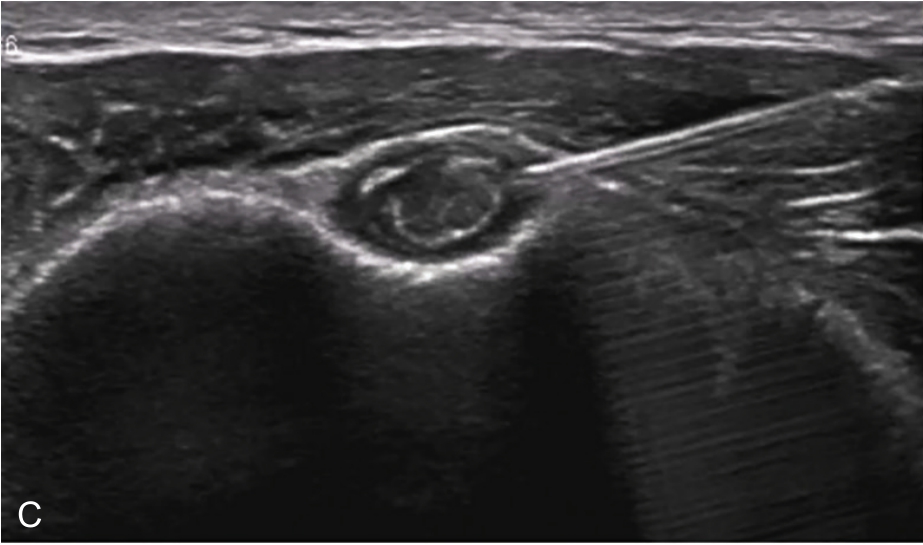

▲ 图2-3-4 超声引导下肱二头肌长头腱鞘介入治疗超声图(一)

A.二维超声:肱二头肌腱鞘内少量积液及滑膜增生;B.超声多普勒:肱二头肌腱鞘内及周围血流较丰富;C.平面内进针法,针尖进入肱二头肌长头腱鞘内;D注射治疗后腱鞘液体增多